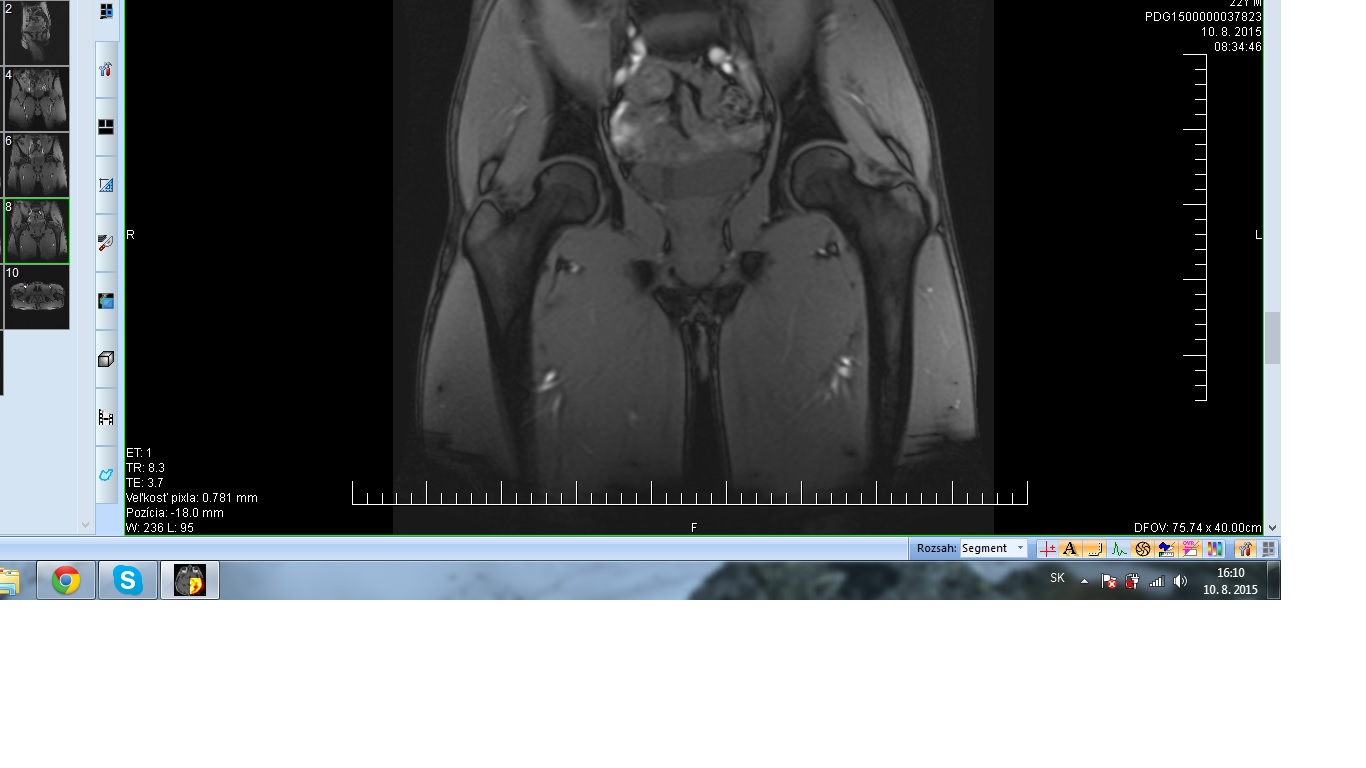

V marci som si privodil unavová zlomeninu krčku ľavého femuru. Pred mesiacom mi ortoped povedal že je to OK. Mňa to však stále bolí...prikladám MR snímok (dnešný). Ak viete pomôžte :)